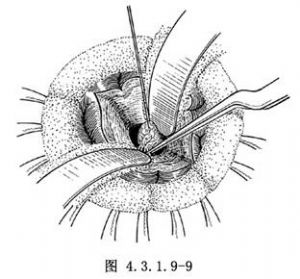

瞭解腫瘤的大小和其與周圍組織的關係,一般對較小而且活動可遊離的腫瘤,在直視下可用1~2針粗絲線穿過瘤體,或用取瘤鉗夾住腫瘤,輕輕向外上牽拉以顯露腫瘤基底部血管,用銀夾夾閉血管和脈絡膜叢,電凝後切斷,再完全遊離腫瘤後完整摘除(圖4.3.1.9-9)。